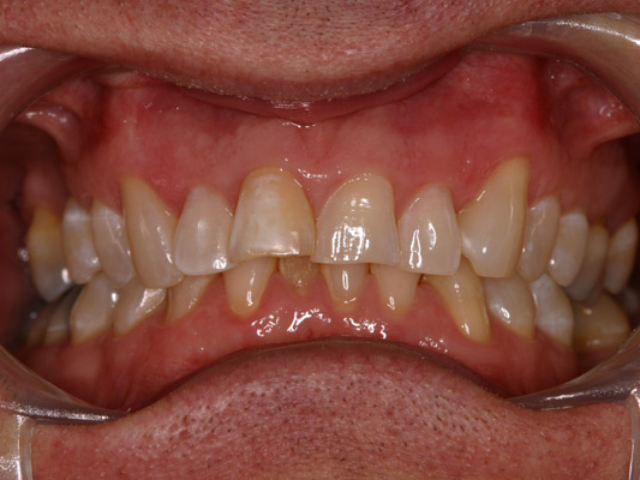

Case Study 14

Problem: This young man was hit by a car while riding his bike. He had multiple fractures in his jaw and three front teeth were fractured.

Plan: Our plan… his fractures were fixed. The trauma left a bony defect which was grafted as well as soft tissue VIP grafts. Placed three separate implants with guided surgery. Molded the tissue and placed Zirconium abutments with porcelain crowns.

A great young man with a confident smile.